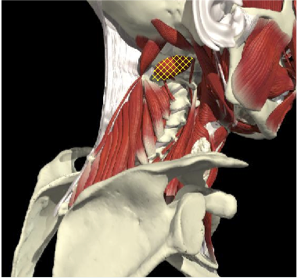

ACCURACY OF LOCALIZATION - SCALENES

ACCURACY OF LOCALIZATION LEVATOR SCAPULAE

LOCALIZATION OF MUSCLES IN DEEPER LAYERS

Layer 1

Layer 2

Layer 3

Splenius Capitis

Semispinalis Capitis

Longissimus Capitus

Semispinalis Cervicis

ACCURACY OF LOCALIZATION – DEEPER LAYERS